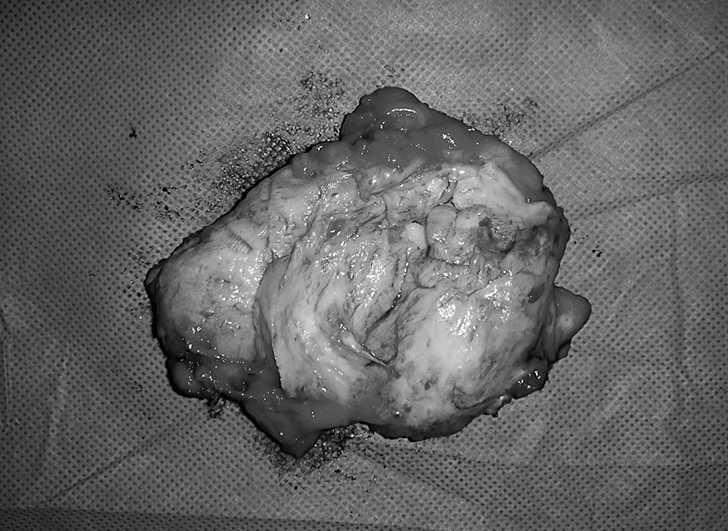

Mujer de 53 años, sin antecedentes de interés, remitida desde el servicio de cirugía general por tumoración en la espalda. La paciente refería dolor periescapular con los movimientos del hombro. En la exploración se observó una lesión abultada en la zona de la punta de la escápula izquierda que aumentaba de tamaño con la elevación y antepulsión del brazo (fig. 3). En la tomografía axial computerizada (TAC) se hallaron dos lesiones bilaterales entre pared torácica y escápulas, de mayor tamaño la izquierda, con apariencia similar al músculo. Lesión muy sugestiva de ED. Se realizó PAAF con resultado de extendido constituido por tejido adiposo. Se solicitó una RMN, que informó de ED bilateral (fig.4). El tratamiento sintomático no logró aliviar el dolor, que comenzó a ser bilateral. Finalmente se realizó una resección marginal de la tumoración sin complicaciones, obteniendo una pieza de aproximadamente 7 x 9 x 4 cm (fig. 5), analizada por anatomía patológica con el resultado de ED.

Figura 5. Resección marginal de un elastofibroma dorsi en la que se aprecia el carácter fibrótico de la tumoración.